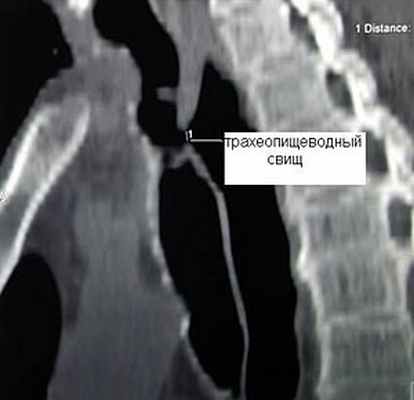

Клиническая диагностика сформировавшегося трахеопищеводного свища, как правило, не вызывает трудностей. Проявляется он приступообразным кашлем, который возникает во время приема пищи. В ранней стадии формирования свища в период проведения искусственной вентиляции легких о его появлении может свидетельствовать внезапное увеличение количества аспирируемого трахеального секрета и тем более появление в нем желудочного содержимого. Подтверждением наличия свища является заброс бария или водорастворимого контрастного вещества при глотании в трахею. Однако уточнение их локализации при небольших размерах свища при рентгенологическом исследовании и эзофагоскопии вызывает существенные трудности. Более информативным оказывается трахеоскопия, при которой удается определить размеры свища, расстояние от голосовых связок и карины, наличие или отсутствие стеноза трахеи и определить характер оперативного вмешательства.

Значительную помощь в выявлении трахеопищевод-ных свищей оказывает также компьютерная томография, которая дает точную информацию о размерах и локализации свища (рис. 2).

Рис. 2. Компьютерная томограмма больного трахеопищеводным свищом

Клиническая диагностика трахеопищеводных свищей, как правило, не вызывает трудностей. Проявляются они приступообразным кашлем, который возникает во время приема пищи. Однако уточнение их локализации при рентгенологическом исследовании с барием и эзофагоскопии вызывает существенные трудности, особенно при небольших размерах свища. Более информативным оказывается трахеоскопия, при которой удается определить размеры свища, расстояние от голосовых связок и карины. Кроме того, значительную помощь в выявлении трахеопищеводных свищей оказывает также компьютерная томография.

![]() Рис.9. Компьютерная томограмма больного с трахеопищеводным свищом. | ![]() Рис. 10. Трахеоскопия больного с трахеопищеводным свищом, осложненным стенозом трахеи. |